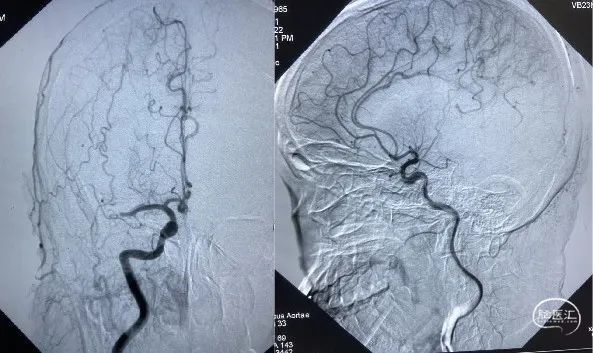

脑血管造影证实:右侧大脑中动脉M1段闭塞。

采用SWIM技术取栓,一把通,远端血流TICI分级3级。

23:25 开始穿刺;

23:35 造影明确右侧大脑中动脉M1段闭塞;

23:55 血管开通成功(距离发病2小时40分钟)。